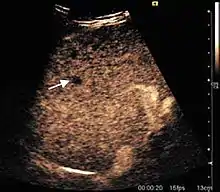

Liver cyst

Hydatid liver cyst. Diagnostic criteria are the presence of membranes and sediment inside.